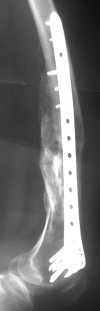

KEMMD> Again, Locking Plating is minimally invasive, SUBCUTANEOUS

KEMMD> INTERNAL FIXATION

Characteristic of locking nailing hardly ever sounds less attractive...

KEMMD> and I believe for the most surgeons preferred

KEMMD> method of treatment for distal femur fractures

A new toy is more interesting and fashionable. And anyway it is not panacea, i have already seen presentations with LISS failures like the attached one presented by D.Seligson. And people also demonstrated incisions say that the method is not so LESS invasive as it supposed to be.